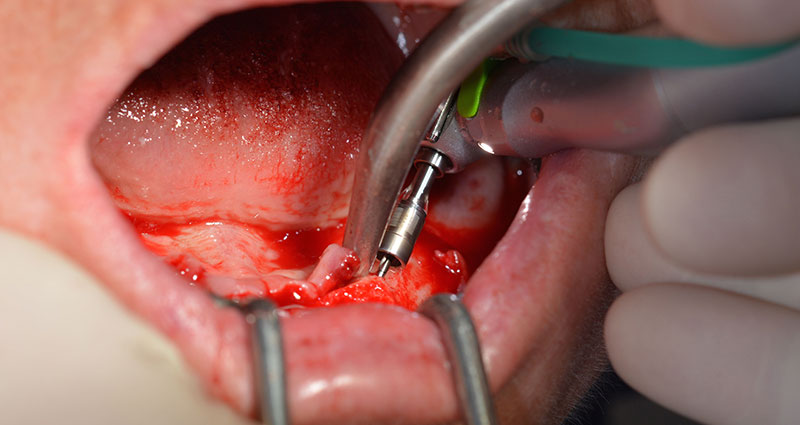

After removal of the residual dentition in the mandible, the alveolar crest was exposed from 37 to 47.

The mental foramen was first identified as a limiting anatomical structure and then the cortical bone of the crest was smoothed with the straight handpiece and a large rose-head bur (Fig. 4).